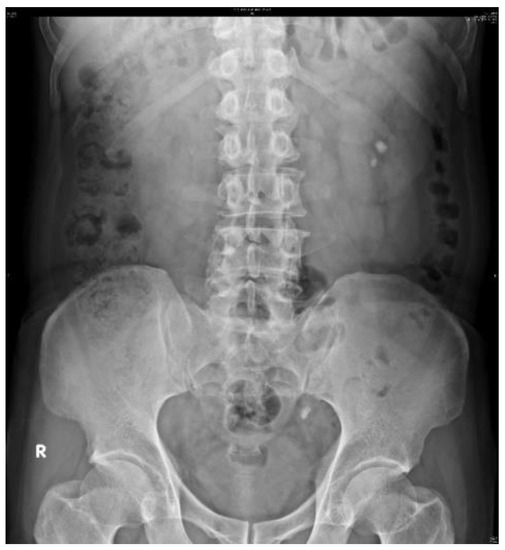

2.2. Datasets

3.4. Subsystem 2—Segmentation Model for Medical Images